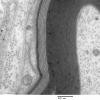

1E2A Anti-MAG NP (Case 1) EM 022 - Copy

1E2B Anti-MAG NP (Case 1) EM 023 - Copy